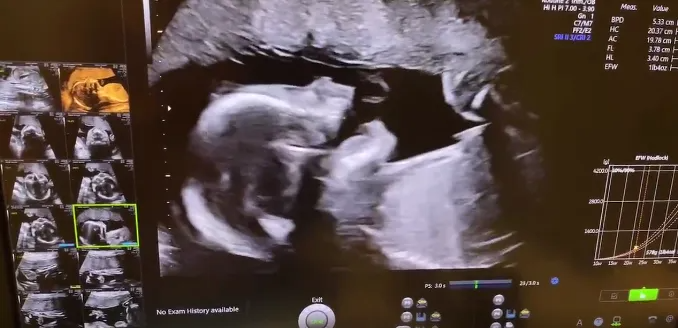

W女士的试管进程非常顺利,但最终子宫检查结果显示,她的内膜厚度一直不理想、激素也不太完美,即便怀孕也有可能流产。她对四处奔波换来的2颗健康胚胎视如珍宝,为了让来之不易的胚胎更好的生长,最终选择了更健康的子宫进行移植。于是就有了我们开头提到的,宝宝在子宫里面调皮的场景,大排畸筛查的结果显示孩子非常健康、心跳非常有力且清晰可见。